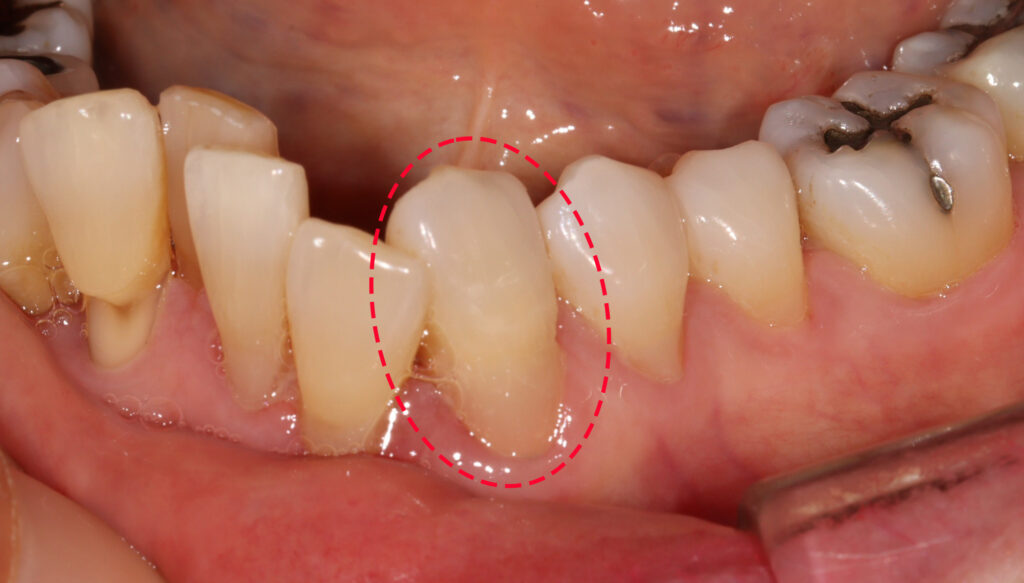

접착력과 마진 형성을 위해 잇몸에 실을 넣어

치은 압배를 진행한 모습인데요.

– 치경부 레진 주요 포인트

1. 치아면을 다듬어서 접착에 유리한 형태로 변화 시킴

2. 접착력을 높히기 위해 치은압배 후 수복

3. 시린 증상을 덜 유발하는 SE bond를 이용해서 접착력을 극대화

4. ** 플로우 레진과 패커플레진을 적절히 레이어링

5. 잇몸을 덮지 않도록 마진을 형성